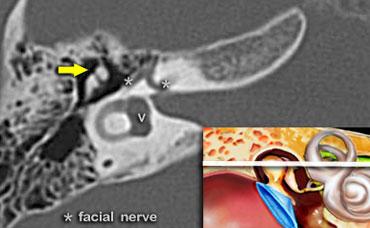

Bên trái, điểm trước nhất của dây thần kinh mặt được thấy (mũi tên trắng).

Tại điểm này, dây thần kinh tạo thành vòng chữ U.

Vị trí này được gọi là genu hay geniculum và đại diện cho hạch gối (geniculate ganglion).

Một lát cắt coronal hơi ra phía sau hơn sẽ cho thấy dây thần kinh mặt hai lần.

Phần phía trong là đoạn thoát ra khỏi ống tai trong và chạy về phía hạch gối (mũi tên trắng phía trong).

Phần phía ngoài là đoạn chạy theo hướng ra sau, xuất phát từ vòng chữ U của gối thứ nhất.